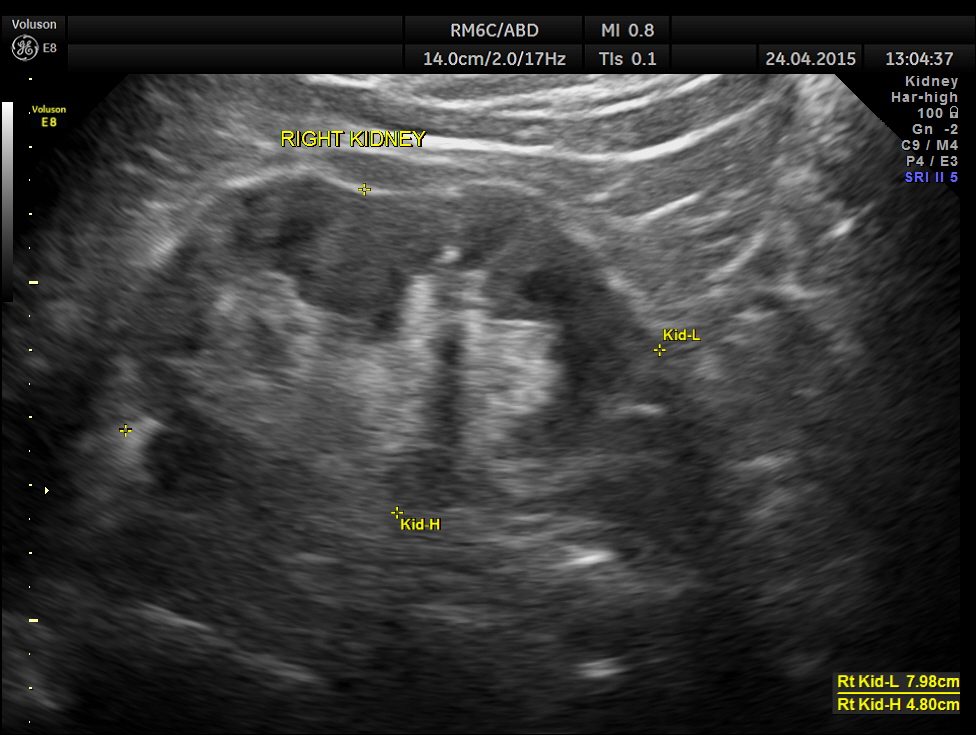

His ultrasound at present showed :

The kidneys show mild pelvi calyceal dilatation.